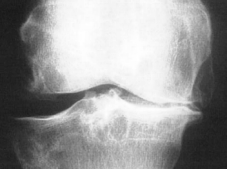

Bei der Arthrose (Bild rechts Kniegelenksarthrose) ist die mechanische Eigenschaft der Gelenkflüssigkeit

erheblich beeinträchtigt.

Diese kann dadurch die Pufferfunktion nicht

mehr erfüllen. Die mechanische Belastung des Gelenkes nimmt zu, der

Knorpel wird überlastet.

In weiterer Folge treten Schmerzen,

Entzündungen und Bewegungseinschränkungen auf.